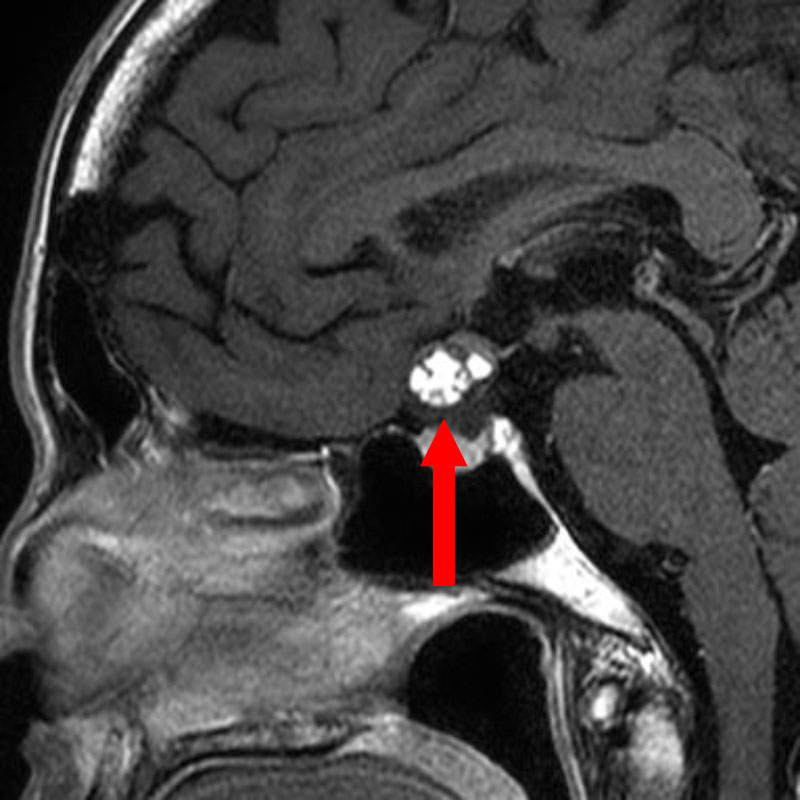

586

'24年10月

50代

下垂体腫瘍

頭蓋内腫瘍摘出術

No.’24_88 手術前1

No.’24_88 手術前2

No.’24_88 摘出 前

No.’24_88  摘出 中

No.’24_88 摘出 後